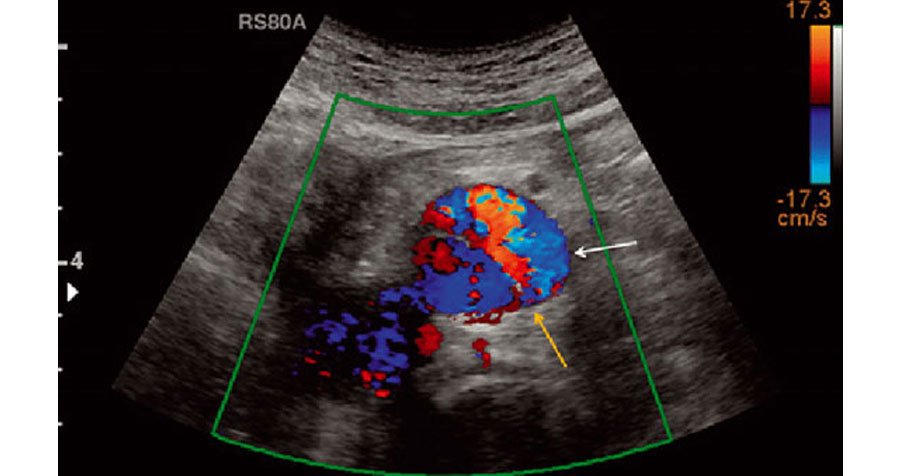

Color Doppler is a diagnostic imaging technique used in ultrasound to visualize blood flow within the body's vessels and organs. By assigning different colors to the direction and speed of blood flow, Color Doppler enables clinicians to assess circulation, detect abnormalities such as blockages or narrowing in blood vessels, and evaluate the function of organs like the heart, liver, and kidneys. This non-invasive procedure is widely utilized in various medical specialties, including cardiology, obstetrics, and vascular medicine, providing valuable information for diagnosing and managing a range of conditions, from heart disease to pregnancy complications.